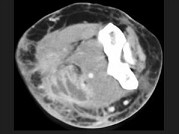

- 单项选择题男,26岁, 肘部红、肿、热、痛,疼痛呈搏动感, 结合图像,最可能的诊断是 ( )

A、脂肪瘤

B、脂肪肉瘤

C、软组织脓肿

D、血管瘤

E、淋巴管瘤